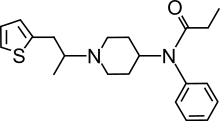

Anilidopiperidines

- 3-Allylfentanyl

- 3-Methylfentanyl

- 3-Methylthiofentanyl

- 4-Phenylfentanyl

- Alfentanil

- α-Methylacetylfentanyl

- α-Methylfentanyl

- α-Methylthiofentanyl

- Benzylfentanyl

- β-hydroxyfentanyl

- β-hydroxythiofentanyl

- β-Methylfentanyl

- Brifentanil

- Butyrfentanyl

- Carfentanil

- Fentanyl

- Lofentanil

- N-Methylcarfentanil

- Mirfentanil

- Ocfentanil

- Ohmefentanyl

- Parafluorofentanyl

- Phenaridine

- R-30490

- Remifentanil

- Sufentanil

- Thenylfentanyl

- Thiofentanyl

- Trefentanil

Structures